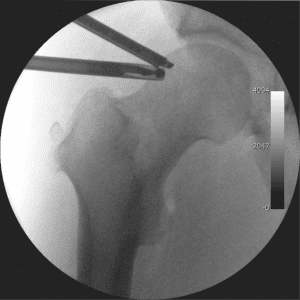

Implanting the CoFlex™

Using fluoroscopic guidance, the Coflex™ implant is inserted through the incision and placed between the spinous processes.